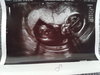

Mogłabyś wrzucić zdjęcie z usg z 13tc gdzie wydaje się że chlopiec?Odgruzowałam swoje zdjęcie z prenatalnych z 13 tygodnia:-) chłopak na 90% ale 10% furtki postawione, no i masz babo placek:-) w 22 tyg kobietka:-)